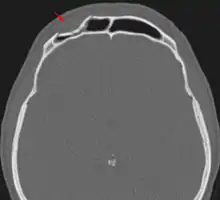

Лобна пазуха зазвичай парна, але рідко симетрична, на рентгенограмах її видно у формі нерівномірних пелюсток, розвернутих тонкою частиною донизу, які відкриваються у відповідні половини носа. Лобна пазуха може бути однією порожниною або мати численні комірки, поділяючи пазуху на окремі відсіки. Перегородка між двома лобними пазухами рідко буває рівна, часто одна пазуха більш розвинена інша пазуха менш розвинена, а у 1 % відсутня з однієї сторони[3]. Комірки та перегородки пазухи вистелені слизовою оболонкою та мають сполучення з порожниною носа. Передня стінка лобної кістки зазвичай дуже тоненька, що часто сприяє вдавленим переломам лобної кістки при травмах голови або умисних ударах у ділянку лоба.